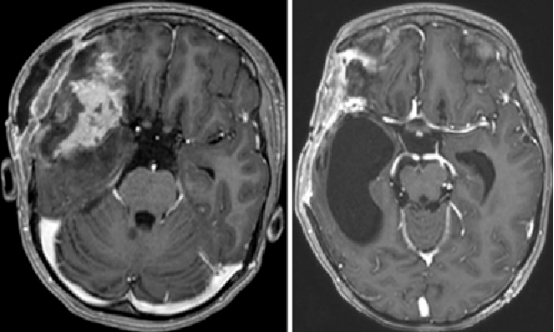

A: 弹簧圈栓塞术后1.5个月,显示右侧额叶残余出血的演变,周围伴有额叶和颞叶脑软化。

B: 栓塞术后11个月,显示右侧外侧裂内有一个2.3 × 2.7 × 1.8 厘米的软组织肿块,包绕右侧大脑中动脉三分叉并累及邻近硬脑膜。

C和D: 术后13个月,显示一个8 × 7.2 × 7 厘米的肿块,包绕右侧大脑中动脉,并延伸至前颅窝和中颅窝。可见明显的占位效应、中线移位及凸面硬脑膜受累。

Rutka教授团队紧急评估后,决定为苏珊实施额颞开颅手术。在神经导航等辅助技术的支持下,手术顺利完成了肿瘤的次全切除。然而,等到术后病理结果出来,所有人都被震惊了——苏珊脑内的这个肿块,被确诊为恶性周围神经鞘瘤(MPNST),一种在儿童颅内极为罕见的恶性肿瘤。进一步的基因检测揭示了背后的重要背景:苏珊的母亲本身有Ⅰ型神经纤维瘤病(NF1)的病史,而苏珊自己也因此被诊断为NF1。

左: 开颅术后第1天,显示肿瘤次全切除术后改变及周围脑软化。